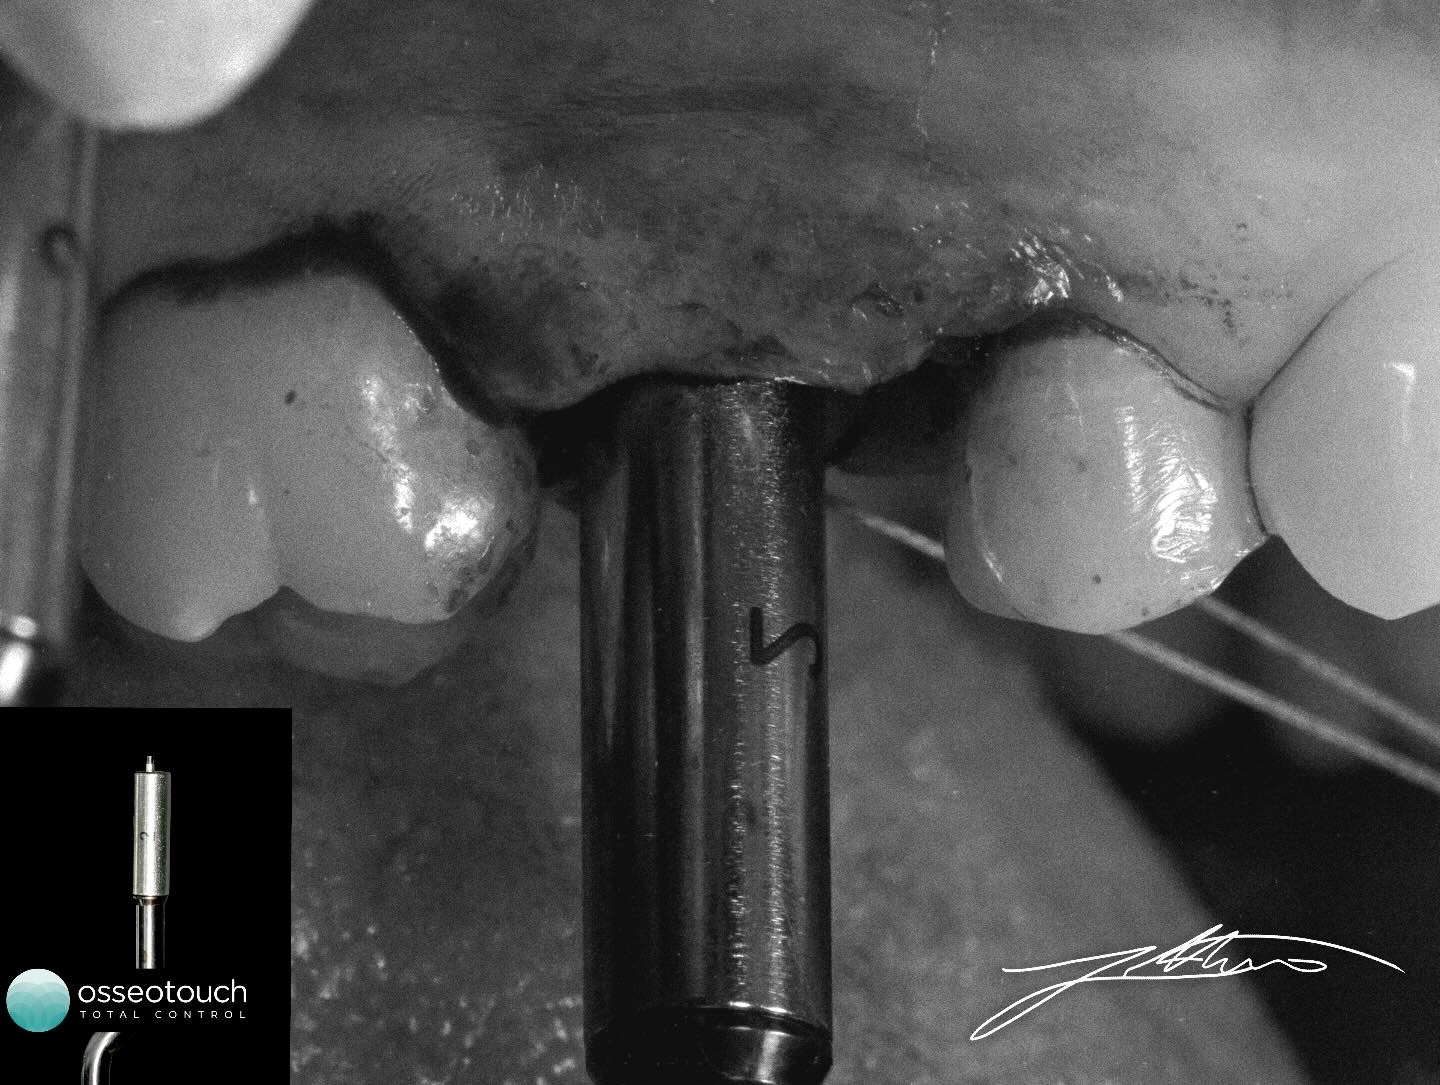

Zgjedhja e teknikës kirurgjikale Në këtë rast, u vendos të aplikohej një qasje krestale, duke shmangur një procedurë më invazive laterale, falë përdorimit të Magnetic Mallet. Objektivi kryesor ishte menaxhimi sa më i sigurt i membranës së Schneider-it, minimizimi i traumës kirurgjikale dhe ruajtja maksimale e indeve përreth. Foto 4 Teknika e zgjedhur synonte: • Rritjen graduale dhe të kontrolluar të lartësisë kockore • Reduktimin e rrezikut të perforimit të membranës së sinusit • Vendosjen e implantit në të njëjtën seancë kirurgjikale • Përmirësimin e komfortit intra- dhe post-operator për pacientin Në këtë kontekst, Magnetic Mallet përfaqëson një evolucion të rëndësishëm krahasuar me osteotomet tradicionale të aktivizuara manualisht.

Përgatitja e vendit të implantit u krye në mënyrë graduale, duke përdorur insertet Elevate të Magnetic Mallet, të pajisura me stopper progresiv, që garantojnë kontroll maksimal mbi thellësinë e penetrimit dhe avancimin vertikal drejt dyshemesë së sinusit maksilar.

• Fillimisht u përdor inserto i parë me stopper 2 mm, duke mundësuar një qasje jashtëzakonisht konservative drejt dyshemesë së sinusit.

• Më pas u vijua në mënyrë sekvenciale me:

o inserto me stopper 4 mm

o inserto me stopper 5 mm

o inserto me stopper 6 mm

o inserto me stopper 7 mm

Ky avancim i kontrolluar u realizua përmes mikro-zhvendosjeve kockore të sakta dhe të parashikueshme, duke respektuar integritetin e membranës së Schneider-it dhe duke minimizuar stresin mekanik mbi strukturat anatomike përreth.